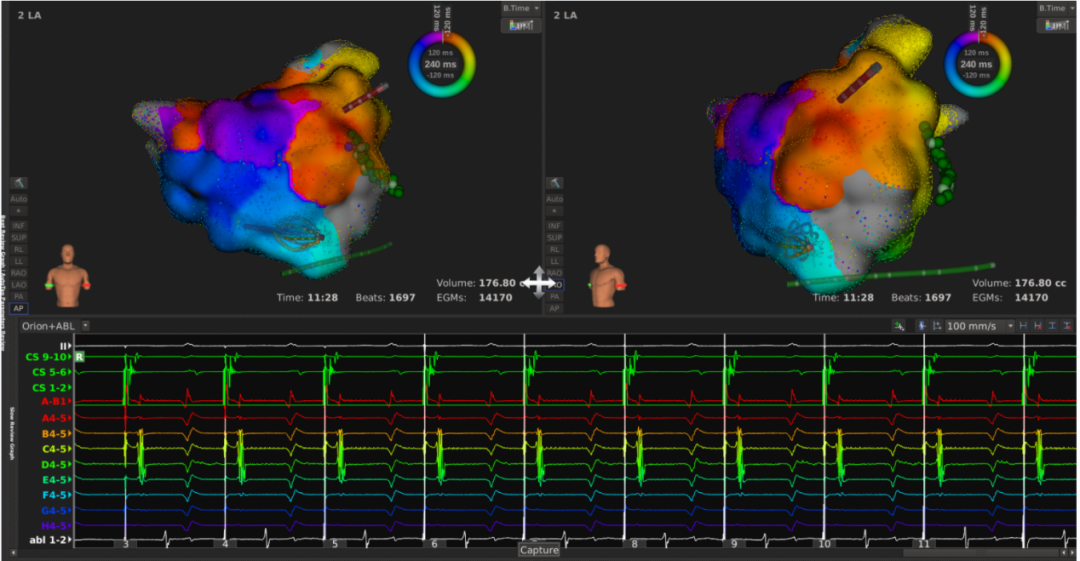

患者上台常规消毒铺巾,心电图显示心房扑动,周长为240ms,穿刺后,先行右房标测,标测结果显示最早激动点由冠状窦口传出,右房整体激动时间占心动过速周长约1/2。遂穿刺房间隔至左房,左房标测结果可见该心动过速绕二尖瓣进行折返,切换电压基质图可见顶部线已断,前壁线区域部分恢复,疤痕部分参与传导。遂先行消融前壁线,以40w 43℃功率模式放电,放电过程中平均单点阻抗下降约25Ω。至前壁线消融结束,心动过速周长延长至260ms. 再行消融二尖瓣峡部线,自瓣环拉至左下肺静脉过程中,DIRECTSENSE™局部阻抗监测技术显示单点阻抗下降约12Ω,心动过速周长逐渐延长至300ms,消融左下肺静脉口蓝点处,心动过速终止。巩固消融后,起博验证,二尖瓣峡线隔离成功。反复burst刺激诱发未见心动过速,本次手术结束。整台手术仅历时90分钟,病人术后感觉良好。

李岳春主任指出该病人病情复杂,能又快又好完成手术,Rhythmia三维标测系统和DIRECTSENSE™(局部阻抗监测技术)起到了关键作用,DIRECTSENSE™提供新的视角以评估导管贴靠,贴靠越好初始阻抗越高;本例手术中前壁线消融每个点阻抗下降10-15Ω,峡部线消融时平均每个点阻抗下降12Ω,DIRECTSENSE™在真实生物反馈的指导下提示有效消融终点,避免过度消融。

7、二峡线消融,于蓝点处心动过速终止

8、CS1-2起搏验证二峡隔离